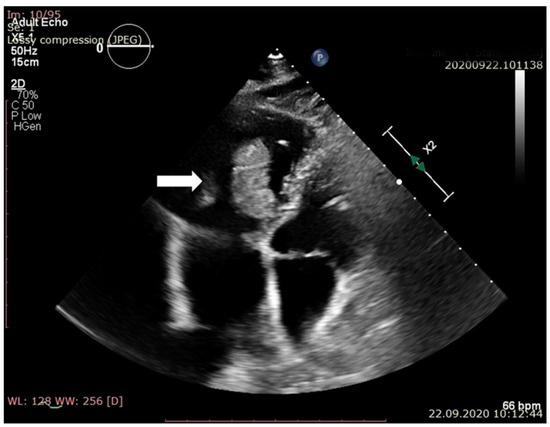

| Macroscopic | Mural trombi, Endocardial fibrosis [23] Monovalvular involvement Mixoid degeneration Valve ulceration or fibrinous mass No fibrin valve deposits [24,25] | Small, warty, sessile vegetations on valve flow surface [26] | Large or small vegetations on valve flow surface [27] | Small or absent vegetations, with a smooth nodular aspect [13] |

| Predilection | Right heart [13] | Mitral, aortic, tricuspid valves [27] | Aortic, mitral valve [33] | Aortic, mitral valves [32] |